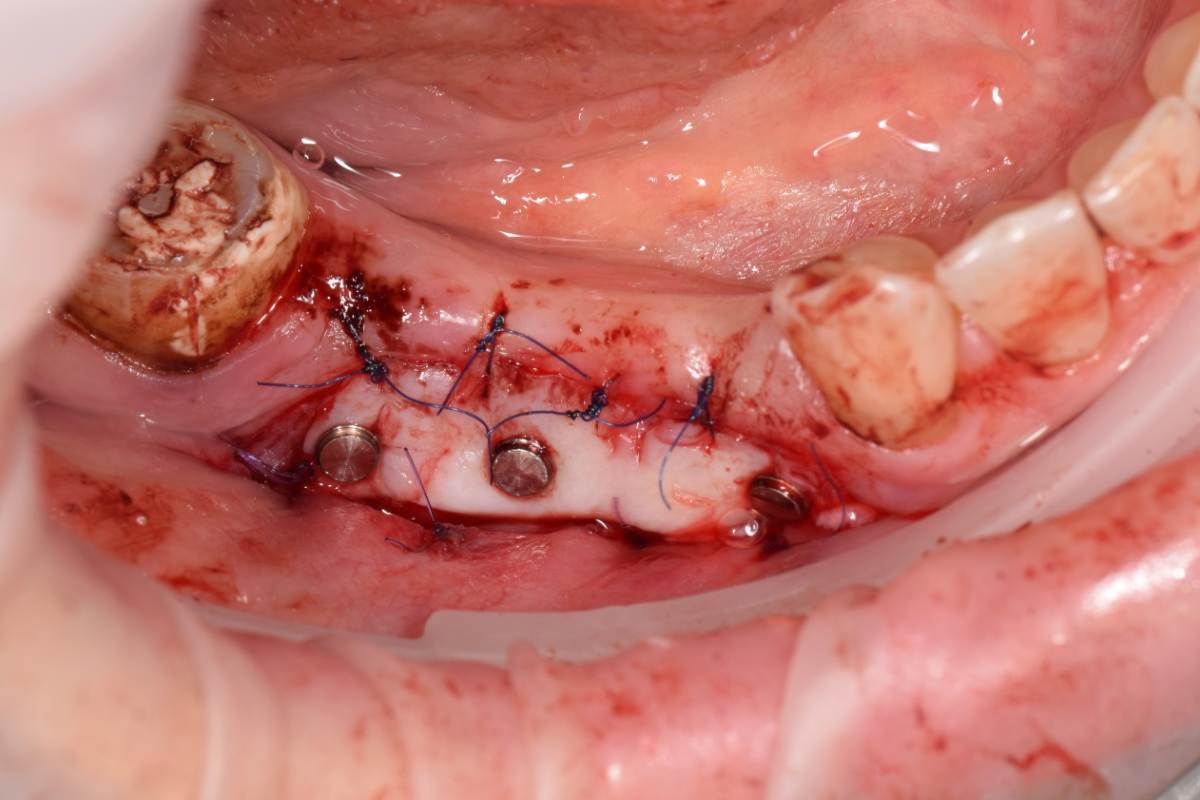

Fin Опубликовано 5 июня, 2025 Поделиться Опубликовано 5 июня, 2025 Здравствуйте коллеги. Хотел бы представить вашему вниманию первую часть кейса по восстановлению 4 сегмента. Перелом зуба 4.5 под мостовидным протезом 4.7-4.4. 4.7 решено оставить до последующего повторного протезирования При планировании имплантации вестибулярное оголение имплантата на 1.5-2мм в области 3. 4. Дефицит керотинизированной слизистой оболочки. Более глубокое положение имплантата приведет к чрезмерному количеству сзизистой оболочки в 7-8 мм. Решено не пытаться использовать ССТ с целью перекрытия оголенного имплантата а попробовать технику морковки профессора Кюри. 1 этап операции. Удаление зуба 4.5, подготовка костного ложа под имплантаты при помощи трепанов и запор костных морковок, установка имплантатов неодент 3.75х10 в позицию 4.4, 4.3х10 в позицию 4.6, ушивание. 2 этап. Создание прикрепленной слизистой. Расщепление лоскута, удаление пиноа, пересадка СДТ с фиксаций его этими же пинами. 3 этап. Открытие имплантатов с установкой ФДМ и снятие швов через 2 недели. Решил не добавлять ССТ. На данный момент ожидаем полное восстановление тканей и приступаем к этапу протезирования. Так как параллельность имплантов достаточна планирую протезировать с уровня имплантатов. 3 2 1 Ссылка на комментарий